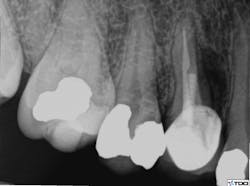

The access cavity and canal walls were examined for fracture or perforation. While a fracture was not observed, a perforation was visualized at the apical extent of the post preparation in the lingual canal. Conventional re-treatment of both the buccal and lingual canals was completed. Careful attention to the irrigation protocol was made in order to prevent extrusion of irrigating solutions outside of the perforated root. The buccal canal was obturated to the canal orifice, and the lingual canal was packed apical to the perforation. A small piece of absorbable collagen material (OraTape, Salvin Dental) was packed into the perforation until a matrix was formed that would keep the repair material confined to the root. The perforation and coronal third of the lingual canal were filled with mineral trioxide aggregate (MTA) (figure 4). The occlusal access was sealed with cotton and Cavit temporary filling material (3M ESPE). The final treatment radiograph shows re-treatment and repair (figure 5).

Figure 4: MTA used to fill the perforation and coronal third of the lingual canal